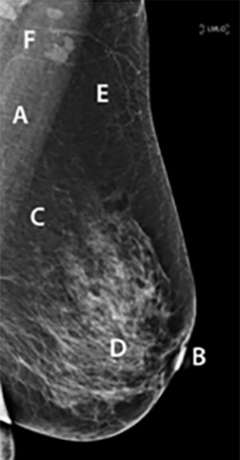

Medio-lateral mammogram of breast preferentially showing pectoralis muscle, glands, some lymph nodes, fat tissue, nipple, and blood vessels